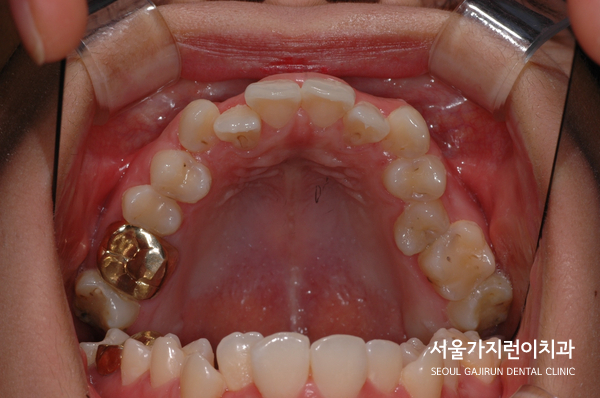

환자분의 경우 상악이 좁아 공간이 부족해 상악 치열이 좋지 않았는데요.

여기에 상악골의 열성장으로 인해 앞니가 거꾸로 물린 상태였습니다. 교합이 어긋나 있기 때문에 저작도 어려운 상태였는데요. 이런 문제점을 보고 저희 치과에서는,

악궁확장장치를 사용해 좁은 상악골을 하악에 맞춰 넓혀주는 교정을 시행했습니다.

이후 미니스크류를 이용해 하악 전체 치열을 후방으로 이동시켰으며 발치한 제 2대구치를 사랑니로 대체해 사랑니를 어금니로 쓸 수 있게 했는데요.

결과적으로 정상교합 달성과 함께 하악 치열의 후방이동도 잘 이루어져 아랫 입술이 들어가 주걱턱 느낌도 많이 개선되었습니다. 이 사진은 치료 종료 후 5년 6개월이 지난 경과 찍은 사진인데요. 이 분의 케이스를 보면 주걱턱도 비수술적인 방법으로 교정했다고 하더라도 장기적 안정성 측면에서 충분히 교정을 할만한 가치가 있다고 보여집니다. 획일적인 방법이 아니라 환자 개인의 특성에 맞춰 치아교정 플랜을 수립했기 때문에 가능한 일이라고 생각하는데요. 맞춤 교정치료를 진행할 수 있는 교정전문치과를 방문해야 할 이유라고 생각이 됩니다.